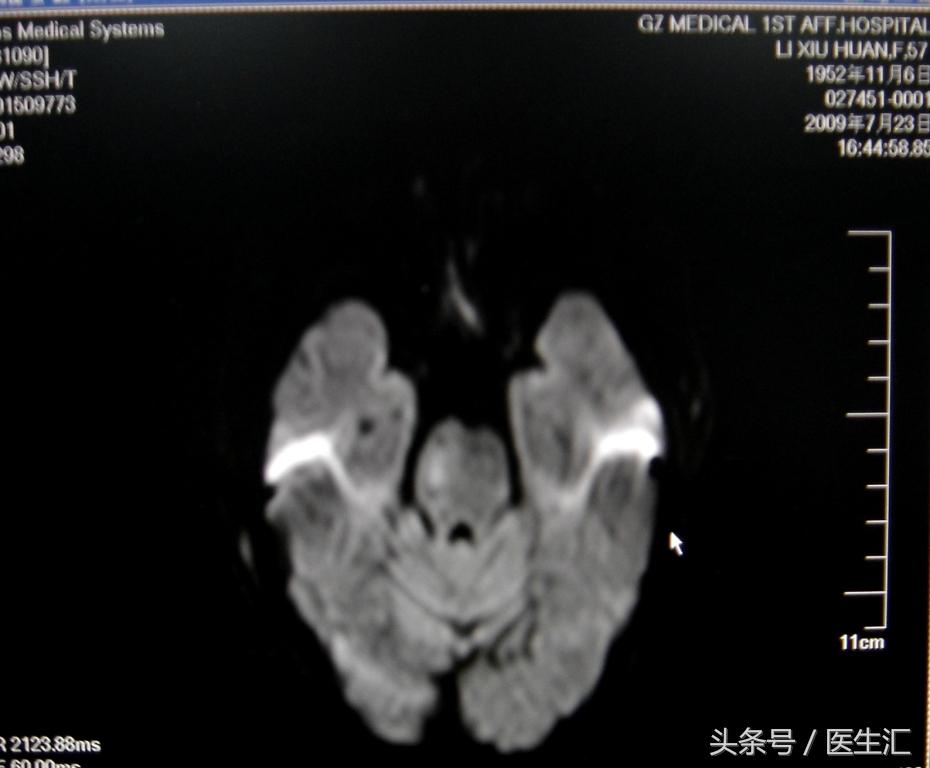

MRI示:左丘脑、左枕叶、小脑蚓部、桥脑急性脑梗塞(见图9)